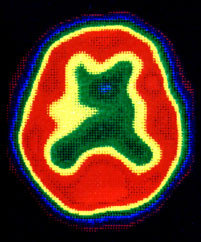

脳血流シンチSPECT(シングルフォトン断層法)

微量の放射線同位元素(ガンマ線放出核種)を静脈注射しどのくらい脳の中に取り込まれるかによって脳血流を測定する

よく使用される薬品は 123I-IMP(N-isopropyl-123I-p-iodoamphetamine)および 99mTc-Ethyl cysteinate dimer(ECD)

([N,N’-Ethylenedi-L-Cysteinate(3-)] Oxotechnetium (99mTc), Diethyl Ester)の2種類です。

さらに、負荷試験と言って脳血管を拡張する作用のあるダイアモックス(diamox)と言う薬を静脈注射してどのくらい脳血流が増加するかを調べます。 この脳血流を測定することによりCTやMRIでは得ることのできない脳の機能的側面が評価できるのです。

正常SPECT像

正常SPECT(ダイアモックス負荷)

青から,黄,赤となるにつれ脳血流量は増加します